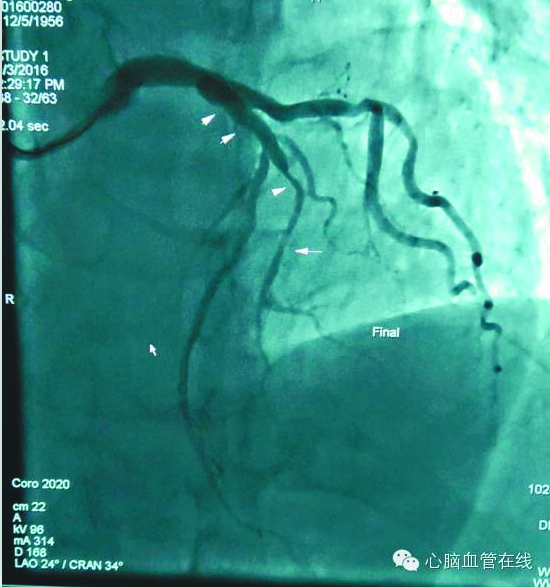

术前造影